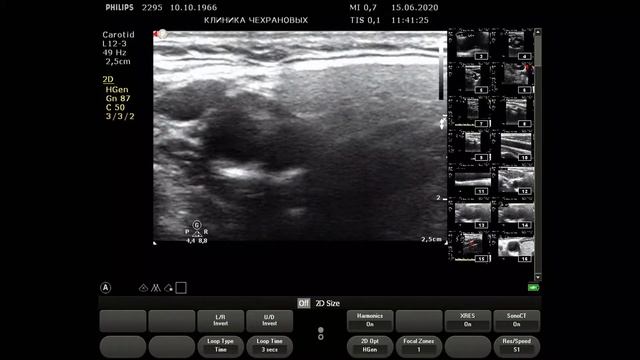

УЗИ БЦА - норма визуализация идеальная. Тот случай когда на обследование БЦА уходит 4 минуты без описания а описание минут 5-6. Для такой категории пациентов 20 минут на вполне достаточно. Но такой пациент скорее исключение из правил. УЗИ сердца - норма. На 12-й минуте - определение индексированного объема левого предсердия определение диастолической функции левого желудочка по тканевому допплеру.,